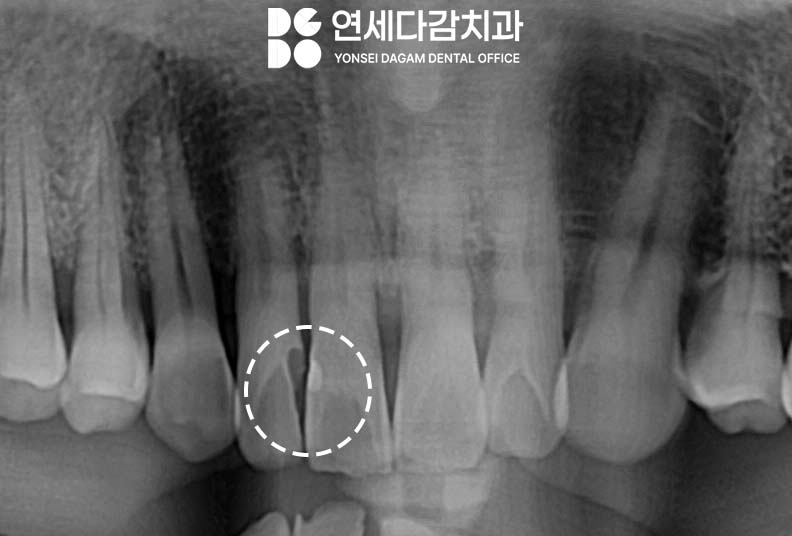

엑스레이를 통한 정밀 검사를 진행하여

손상 범위와 신경손상 여부,

그리고 치아 뿌리 끝에 병소를 확인하고

환자가 느끼는 불편감이 없다면

레진 치료로도 충분하다고 판단합니다.

충치가 얕은 것은 아니지만

치아 구조가 충분히 남아있고

뿌리가 건강하다면 치아 전체를

씌울 필요는 없습니다.

이렇게 치아와 치아 사이에

생기는 충치를 인접면 우식이라고 하는데,

앞니의 경우 다른 치아 보다

두께가 얇기 때문에,

충치가 깊어지면서

앞뒤로 치아를 관통하여

협설면까지 이어질 수 있습니다.